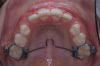

The following case illustrates the complete surgical/orthodontic treatment sequence for an impacted maxillary right central incisor. An 8½-year-old patient presented with a chief complaint of crowded teeth. The maxillary left central incisor was the only erupted incisor at the time of consultation (Figure 2 and Figure 3). Crowding was clinically diagnosed visually by the prominence of the unerupted right central incisor in the vestibule, and this was confirmed with a panoramic radiograph (Figure 4).

Fig 3. Initial situation of case involving an impacted maxillary right central incisor, frontal view (Fig 2) and occlusal view (Fig 3).

Figure 3